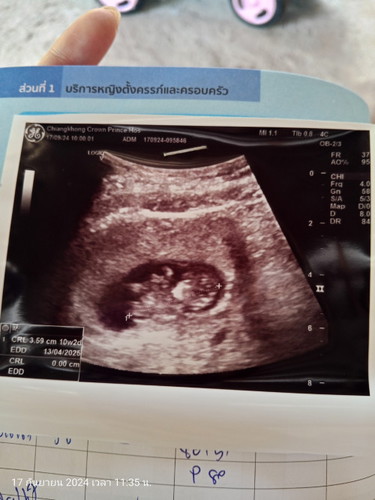

อยากสอบถามว่าอายุครรภ์10w2d ยาว 3.59ซม ตัวเล็กไปมั้ยคะ#ขอบคุณล่วงหน้าสำหรับความคิดเห็นค่ะ

น่าจะปกตินะคะ ทางนี้ 11w5d 4.49 ซม .ค่ะ ตอนไปซาว